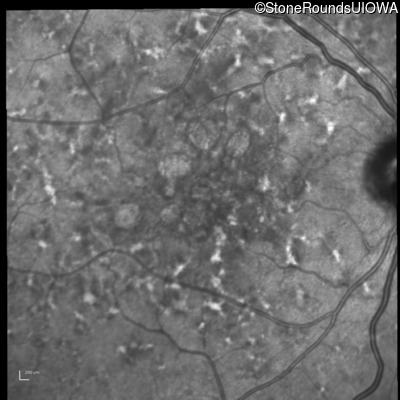

Age at visit: 49 years

This 49 year old man was first told he had a fundus abnormality on a routine eye exam at age 34. Ten years later he noticed some distortion just superior to fixation.

Pattern Dystrophy PRPH2 Gln239Stop CAG>TAG   AD